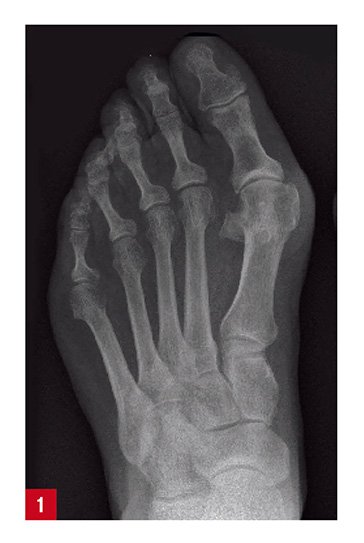

Ein Hallux valgus (auch Ballenzehe oder Schiefzehe) bezeichnet eine Fußfehlstellung, bei der die Großzehe (der Hallux) nicht mehr geradesteht, sondern nach außen zur zweiten Zehe abfällt. In schweren Fällen ist der Nagel der großen Zehe nach innen gedreht. Die Betroffenen leiden an Schmerzen im großen Zeh (Großzehenballen) und haben oft Schwierigkeiten beim Gehen.

Nach einer Anamnese und einer gründlichen ersten Untersuchung wird eine Röntgenaufnahme des gesamten Fußes gemacht, anhand derer festgestellt werden kann, ob es sich bei Ihren Beschwerden um einen Hallux valgus handelt. Anschließend legen unsere Spezialisten in Absprache mit Ihnen die für Sie beste Behandlung fest.

Die Therapie des Hallux valgus kann konservativ oder operativ erfolgen und wird individuell nach einer gründlichen Untersuchung des Fußes mittels Blickdiagnose und Röntgenbild mit unseren Orthopäden besprochen.